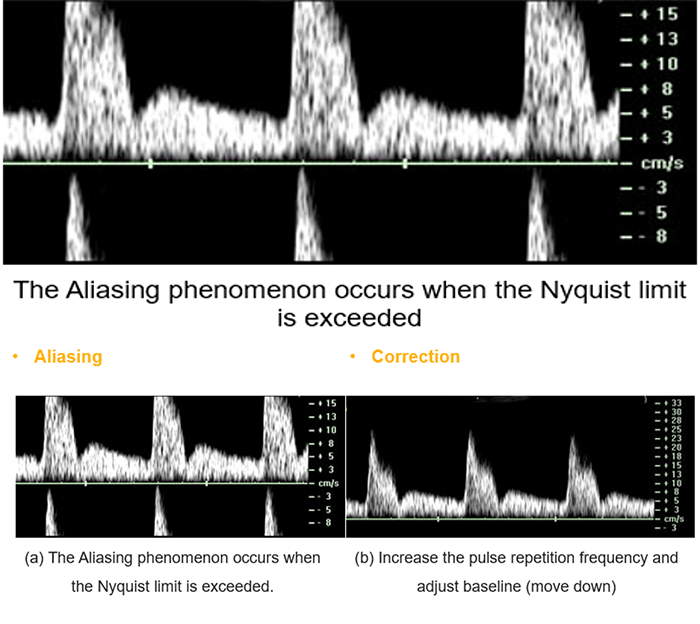

Unfortunately, the pulsed Doppler system presents many disadvantages. First, this system is unable to measure high velocities. Second, pulsed wave systems suffer from a fundamental limitation, which is the aliasing artifact.

Aliasing

Pulsed Doppler systems suffer from a fundamental limitation. When pulses are transmitted at a given sampling frequency, the maximum Doppler frequency that can be measured is half the pulse repetition frequency, also known as the Nyquist theorem. If the blood velocity and the adapted beam/flow angle give a Doppler frequency value greater than half of the pulse repetition frequency, ambiguity in the Doppler signal occurs. This ambiguity is known as aliasing.

Aliasing occurs when the Doppler shift of the moving blood is higher than half of the pulse repetition frequency. Aliased signals are presented in the wrong direction (blue instead of red and vice versa). In this example the measured speed (2.3 m/s) is greater than half of the Nyquist limit (0.64 m/s), thus instead of being colored in red, it will be presented in blue as if the RCB is moving away from the transducer.